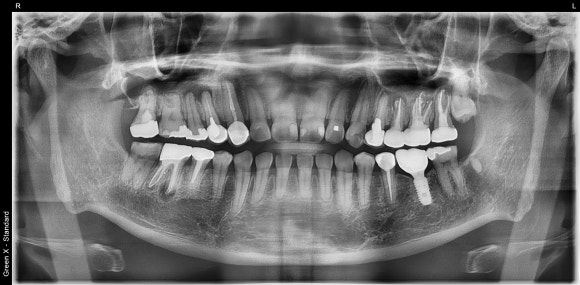

20240411

다수의 치아에 신경치료를 받으셨습니다.

신경치료 받은 치아 중 대부분은

뿌리 끝에 염증이 재발되어 있었습니다.

엑스레이 상에 염증이 보인다고 해서

모두 치료를 해야 하는 것은 아닙니다.

(물론 사이즈가 지나치게 크거나, 인접 해부학적 구조물을 위협하는 경우엔 치료를 권합니다)

가장 중요한 것은 환자분의 불편감입니다.

불편감, 더 나아가 통증이 있을 경우 주치의는 치료를 고려하게 됩니다.